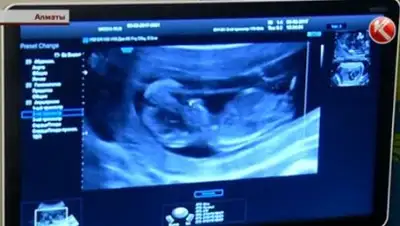

Для того чтобы повысить грамотность казахстанских врачей УЗИ, в Алматы пригласили турецкого специалиста. Ахмет Арда Лембет говорит, что при раннем исследовании ультразвуком можно выявить до 60 процентов заболеваний ребенка. У женщины, которую профессор сейчас обследует, большая проблема. У малыша две патологии: порок сердца и расщелина верхней губы и неба.